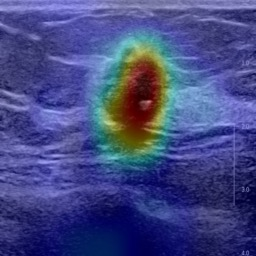

Ultrasonography is an important routine examination for breast cancer diagnosis, due to its non-invasive, radiation-free and low-cost properties. However, it is still not the first-line screening test for breast cancer due to its inherent limitations. It would be a tremendous success if we can precisely diagnose breast cancer by breast ultrasound images (BUS). Many learning-based computer-aided diagnostic methods have been proposed to achieve breast cancer diagnosis/lesion classification. However, most of them require a pre-define ROI and then classify the lesion inside the ROI. Conventional classification backbones, such as VGG16 and ResNet50, can achieve promising classification results with no ROI requirement. But these models lack interpretability, thus restricting their use in clinical practice. In this study, we propose a novel ROI-free model for breast cancer diagnosis in ultrasound images with interpretable feature representations. We leverage the anatomical prior knowledge that malignant and benign tumors have different spatial relationships between different tissue layers, and propose a HoVer-Transformer to formulate this prior knowledge. The proposed HoVer-Trans block extracts the inter- and intra-layer spatial information horizontally and vertically. We conduct and release an open dataset GDPH&GYFYY for breast cancer diagnosis in BUS. The proposed model is evaluated in three datasets by comparing with four CNN-based models and two vision transformer models via a five-fold cross validation. It achieves state-of-the-art classification performance with the best model interpretability.